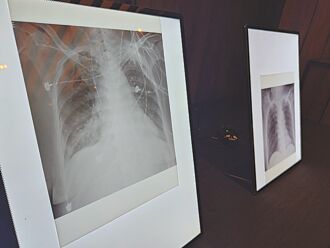

1/3流感家人傳播 老幼要當心

一位61歲糖尿病患者長期血糖控制不佳,年初因肺炎住院,治療後病況稍有起色,原以為即將出院,沒想到患者突發呼吸急促、胸悶,X光顯示右下肺再度出現嚴重感染,確診為流感,追查發現感染源疑似是來探病的家人。醫師指出,三分之一的流感傳播發生在家庭,當病毒在家庭內部快速傳播,幼童與長者往往成為最脆弱破口。